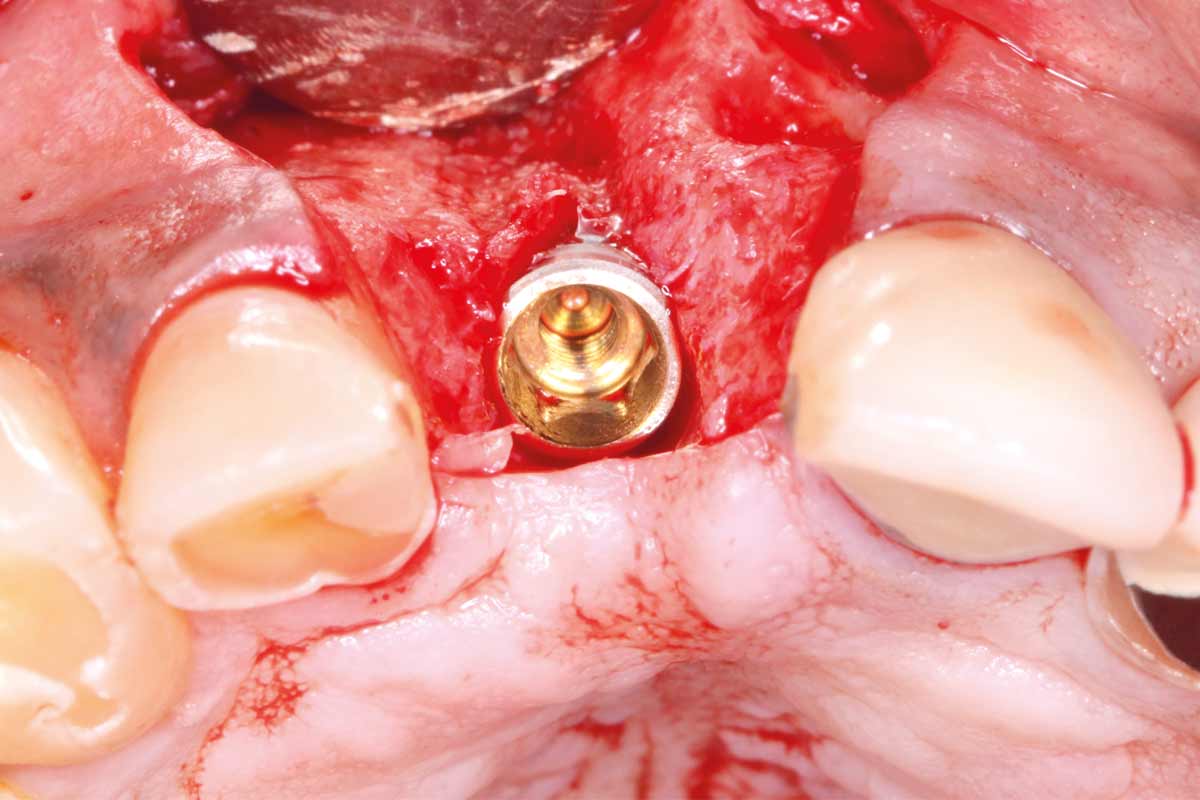

Implant placement and bone augmentation in the aesthetic zone using maxgraft® and permamem® - Dr. A. Puišys

Implant placed in the deficient site. permamem® in place for covering.